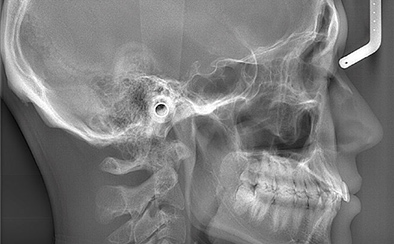

マウスピース矯正では治療前には各種設備を用いた検査、および治療のシミュレーションを行います。当院では歯科用CT、セファロ、口腔内スキャナー(iTero)などの各種先端機器を取り揃えており、精度高く検査した後、シミュレーションや治療計画の作成などに役立てております。

歯科用CT

セファロ

精密検査

セファロや口腔内スキャナーを用いたデータ取得、口腔内や顔貌の写真撮影、模型の作製などを通じて、患者さんの状態を把握するために精密検査を行います。